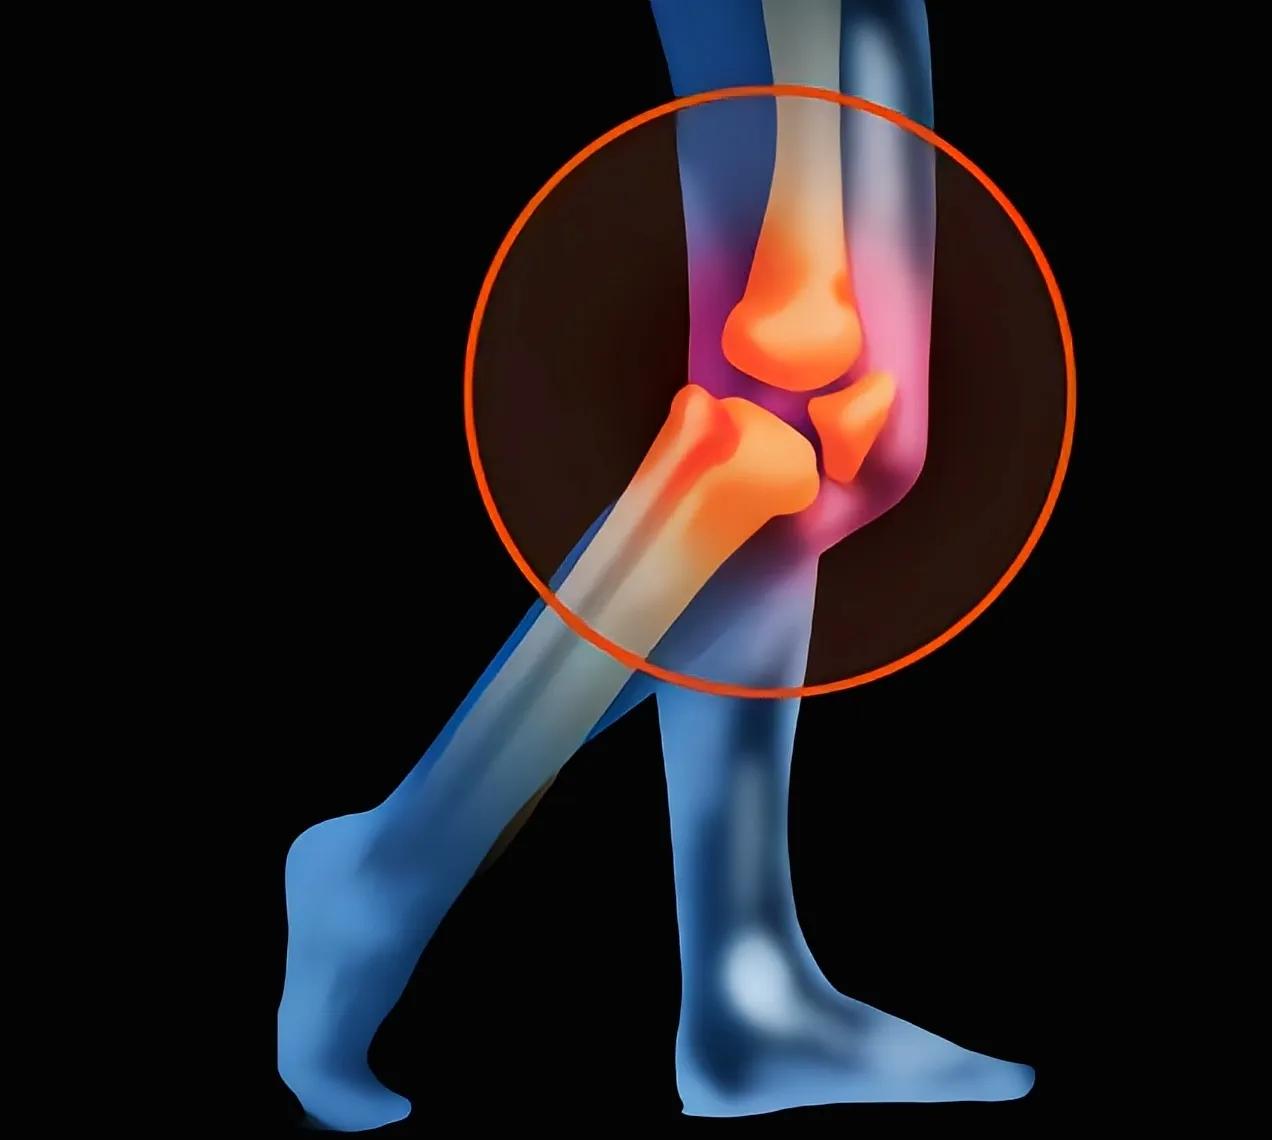

1.踢球为何容易受伤

踢球是一项激烈的运动,常常会导致膝盖受伤。这是因为在踢球过程中,膝盖承受着巨大的压力和扭力,容易受到外力的冲击。而且,由于踢球时需要频繁转身、急停、跳跃等动作,这些运动对膝关节的稳定性要求很高,稍有不慎就可能造成损伤。